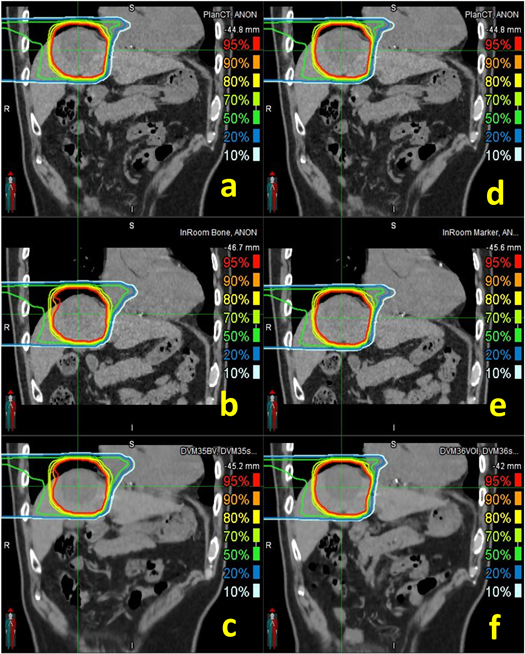

A summary of the dose distribution comparison between the DVM CT and in-room CT for each HCC patient is shown in figure 6, tables 1 and 2. Moreover, the dose distribution of a representative patient is illustrated in figure 7. Between the in-room CT and DVM CT, the PTV coverage (V95%) differences were less than 3%, except for Patient 1 in the BM scenario and Patient 2 in the TM scenario, and the normal liver (total liver minus GTV) dose differences (V20Gy(RBE) and V10Gy(RBE)) were less than 2% (V20Gy(RBE) and V10Gy(RBE) were 0.28 ± 0.62% and 0.14% ± 0.68% for BM and 0.20 ± 0.26% and 0.08 ± 0.30% for TM, respectively). The gamma passing rates with a 3%/3 mm criterion were above 90% in all cases and above 96%, excluding Patient 1.

Figure 7. Isodose lines of bone (left column) and tumor (right column) matching scenarios in PlanCT ((a) and (d)), InRoom-BM (b), DVM-BM (c), InRoom-TM (e), and DVM-TM (f) for Patient 3.

Download figure:

Standard image High-resolution imageFor Patient 2 in the TM scenario, the PTV coverage of the InRoom-TM was significantly lower than that of the InRoom-BM, unlike the other nine cases, which were approximately equal. This may be because the marker shifts inside the liver did not always represent the motions of the entire liver and/or tumor; the distance between the isocenters of BM and TM in the in-room CT and the DVM CT was different by 4.2 mm ( in figure 6(d)) for Patient 2, i.e. the isocenter position of TM in the in-room CT was considerably different from that determined by DVM CT. Applying the difference to determine the new isocenter for InRoom-TM, the new dose distribution for InRoom-TM (InRoom-TMnew, called Patient 2a) could be obtained by recalculating the dose based on the new isocenter. By comparing InRoom-TMnew to DVM-TM, the PTV coverage difference decreased to 0.25%, which was considerably lower than the PTV coverage difference between InRoom-TM and DVM-TM (−8.45%). Conversely, obtaining the new dose distribution the same way as the above for DVM-TM (DVM-TMnew, called Patient 2b), the PTV coverage difference between InRoom-TM and DVM-TMnew decreased to 4.46%. The PTV coverage comparisons between PlanCT, InRoom-TM, DVM-TMnew, InRoom-TMnew, and DVM-TM for Patient 2 are presented in figure 6(e).